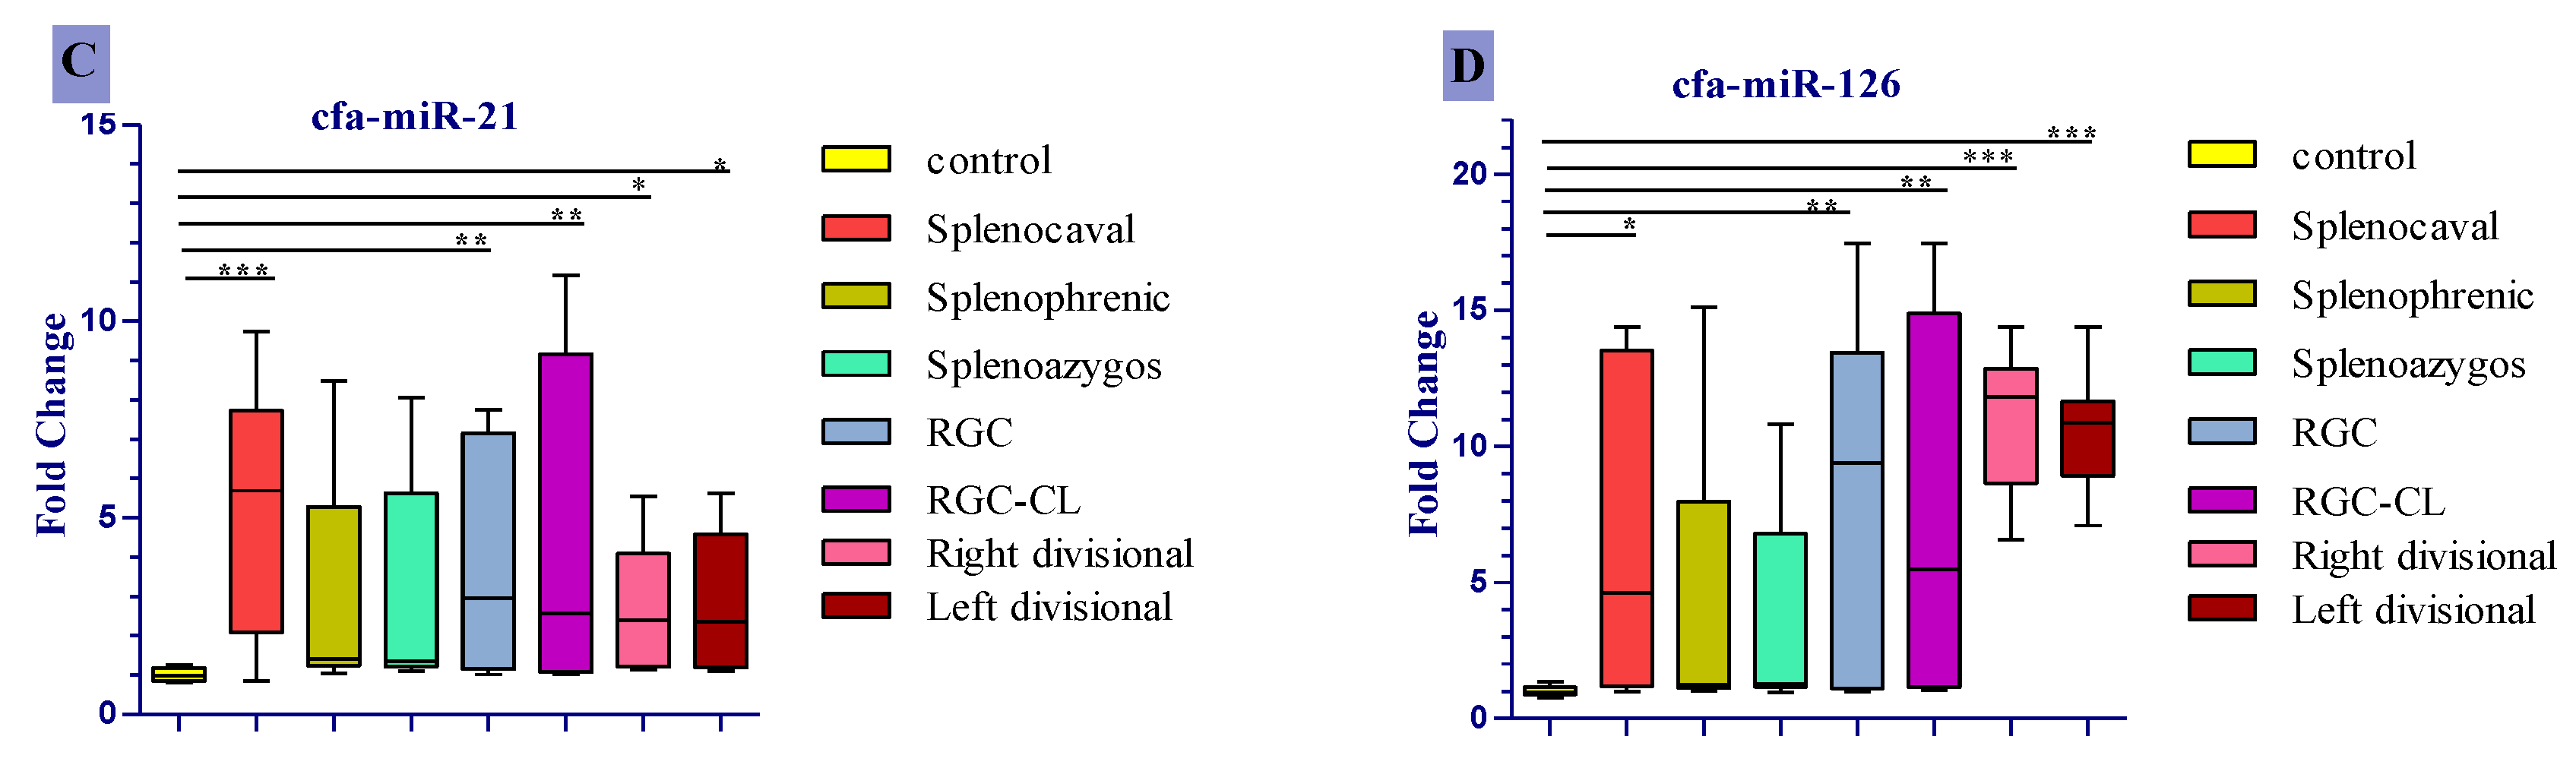

3.4. Expression Profile of the Studied Cfa-Mirnas in the Investigated Groups Compared to the Control Group

3.5. ROC Curve Analysis of Differentially Expressed Serum miRNAs